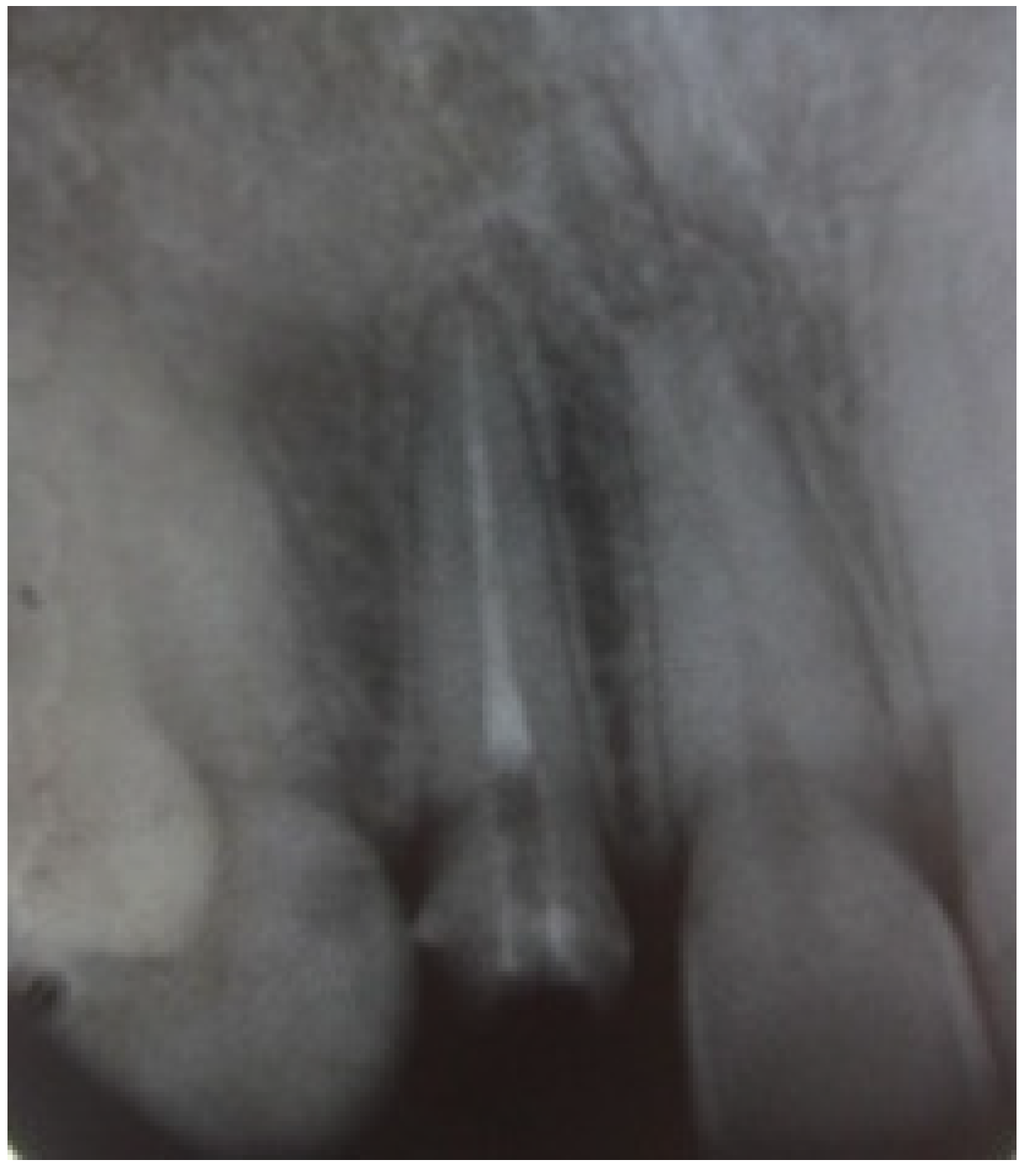

The margin level of the lateral incisor was planned to be 1 mm coronal to the central incisor. The waxed cast served as a guide for provisional restoration which had been optimized after the periodontal therapy until the objectives desired in the final restoration were achieved. The old crown was removed and the remaining tooth structure was evaluated as sound. Radiological reevaluation showed an adequate distance between the bone crest and the residual dental tissue (>3 mm) including biological width (Figure 3).

Figure 3. Radiological reevaluation showing the distance between crestal bone and inter proximal preparation level.